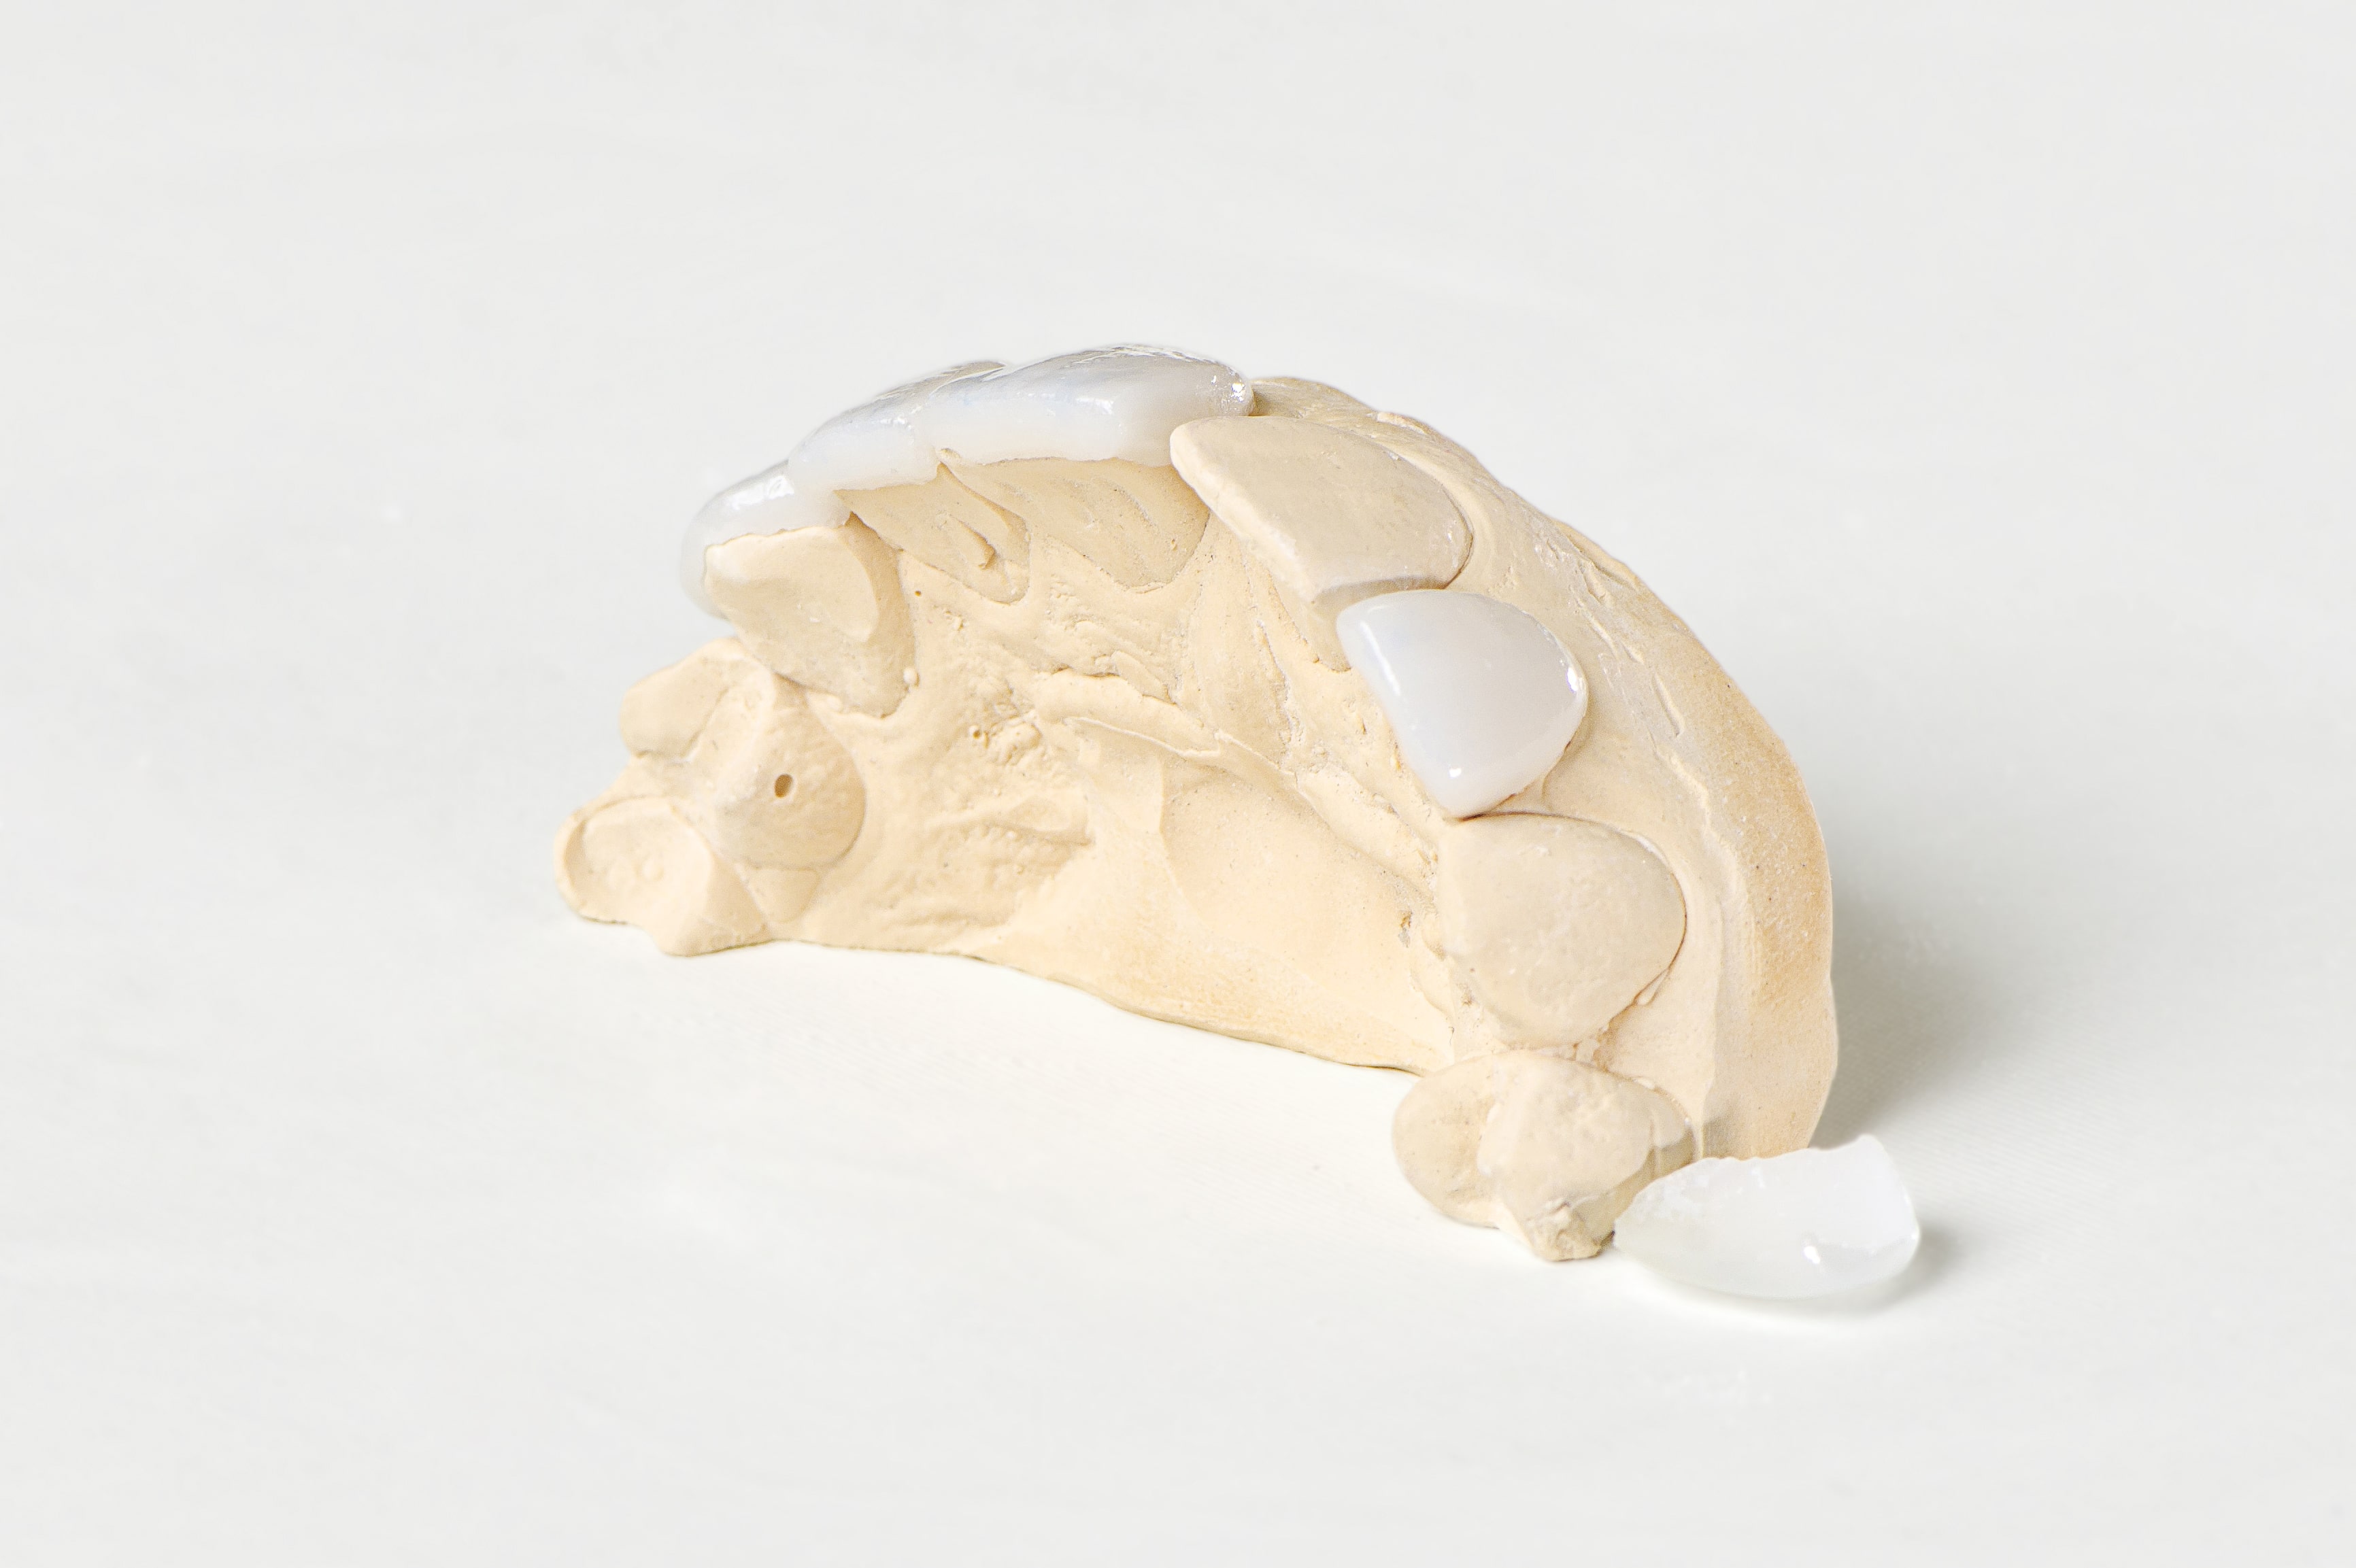

das variiert von Zahnarztpraxis zu Zahnarztpraxis. Wir schildern euch unseren Verlauf – am Beginn steht in der Regel eine Planungsphase – ein sogenanntes WaxUp. Es wird von deinen Zähnen ein Gipsmodell hergestellt, wo dann die Veneers aus Wachs angefertigt werden. So kannst du dir die Situation besser vorstellen. WaxUps werden vorallem dann hergestellt, wenn die Zahnstellung und die Zahnform stark verändert wird.

Am Ende der Präparation erfolgt der Zahnabdruck und die Bißnahme. Die provisorische Versorgung erfolgt mit Kunststoffveneers, diese werden unmittelbar nach dem Abdruck angefertigt. Der Zahntechniker benötigt ca. 3 Tage für die Herstellung der eigentlichen Veneers. Bei der Veneer Übergabe werden die Kunststoffprovisorien entfernt und die Zahnstümpfe gereinigt. Die Klebung kann mit und ohne lokal Anästhesie erfolgen. Nach dem Einsetzten der Veneers werden Kleberüberschüsse penibel entfernt und die Oberflächen poliert.

Wieviel und ob überhaupt etwas von der Zahnsubstanz entfernt werden muss, hängt von deiner Zahnstellung, deinen vorhandenen Zahnfüllungen und deiner Zahnfarbe ab. In der modernen Zahnheilkunde können Zähne durch solche minimal invasive Eingriffe korrigiert werden, Kronenbeschliffe sind nur mehr selten nötig – solch ästhetisch hoch anspruchsvolle Arbeiten erfordern aber ein gut eingespieltes Team (Zahnarzt, Zahntechniker und Assistentinnen). Aus diesem Grund haben wir die Zahntechnik, die Cad/Cam Fräßen und den 3D Drucker im eigenen Haus. Wir bilden den gesamten Zahnersatzfertigungsprozess im eigenen Haus ab, der ausführende Zahntechniker sieht zubeginn, während der Therapie und bei der Übergabe zu, er ist bei jeder Anprobe dabei und auch nach der Klebung sehen wir uns das Ergebnis gemeinsam an.